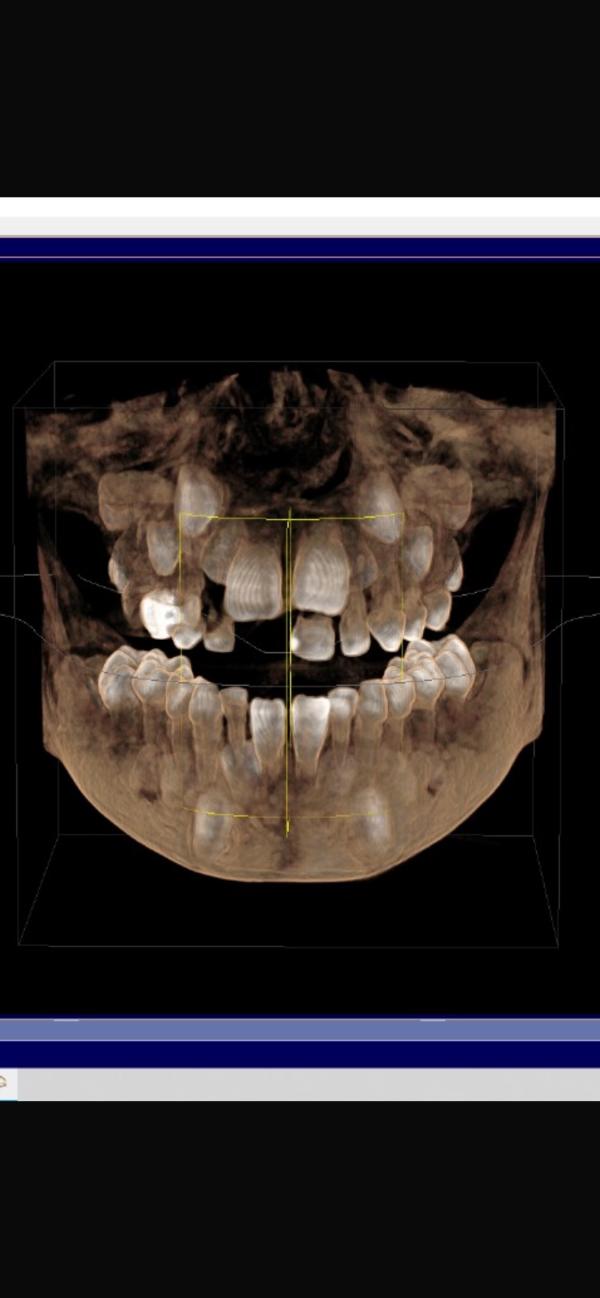

На фото - моё дитя сегодня на консультации у ортодонта. Пошли потому, что у него вылезли шестерки (те, что сразу коренные жевательные), точнее они прорезались, но на них ещё «капюшон» из десны.

Сменились два нижних резца, выпал один верхний, шатается тот, что рядом с ним и ещё один, боковой. Уже второй врач говорит о том, что сейчас это распоостраненное явление среди детей его возраста. На снимке видно, что верхний ряд скученный, резцы и клыки в тесноте, подвывернуты...